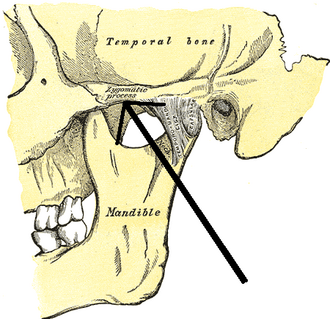

step 7 : perform the tripod osteotomy and expand the width of the orbitals, but something is confusing me about the tripod, how you gonna make lateral orbital rims more setback without causing conflict/problems with the zygomatic arch?

step 7 : perform the tripod osteotomy and expand the width of the orbitals, but something is confusing me about the tripod, how you gonna make lateral orbital rims more setback without causing conflict/problems with the zygomatic arch?